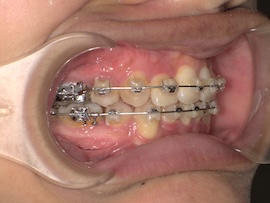

そして1ヶ月後、

牽引のため内側の装置が新しくなりましたが、これがびっくりするくらい話しづらいです…。

元々装置はついていたので案外大丈夫かと思っていたのですが、想像以上の違和感でした。

また、異物を感じているのか明らかに唾液の量が増えた気がします。(笑)

慣れるのかどうか本当に不安で先生にも「完全には慣れないかもしれない」と言われたものの、1週間くらいすれば気にならない程度には慣れました。口の中ってすごいですね。(笑)

準備ができたのでいよいよ数日後に開窓(歯茎を切って埋まっている歯にボタンをつけてもらうこと)を他院で行います。